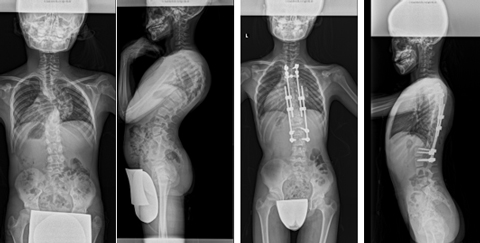

重度脊柱変形に対する矯正固定術

さまざまなお体の病気に伴い、せぼねが重度に変形を起こし息切れなどの症状が出る場合があります。

これらの患者様に対しては状況に応じて、せぼねを矯正固定する場合があります。小児科やリハビリテーション科と相談しながら手術時間や入院期間を検討していきます。